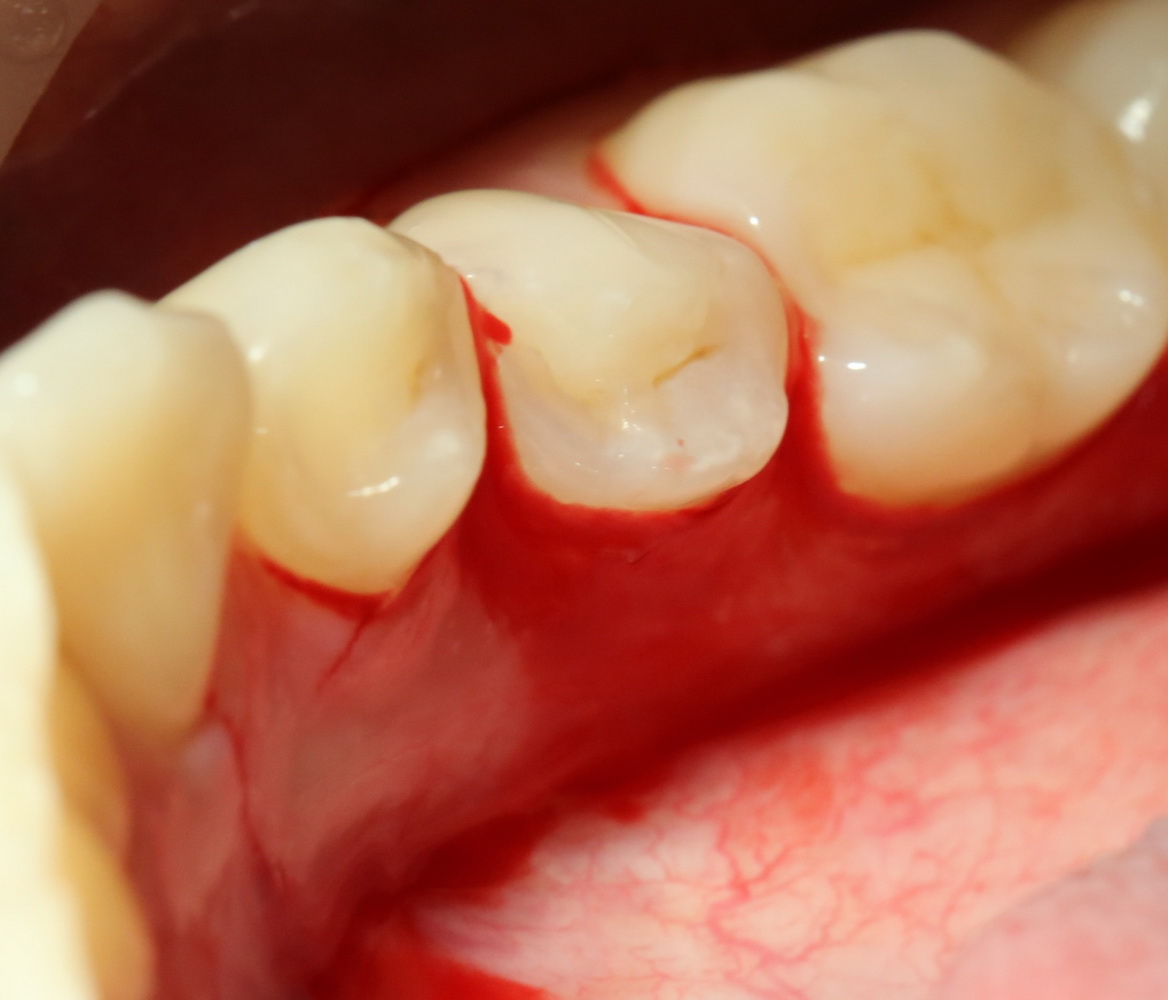

Всё начинается с анестезии и разреза:

Его приблизительная схема показана на картинке справа. Разрез спланирован таким образом, чтобы потом вывести узелки швов на внешнюю сторону — так они будут меньше беспокоить пациента в послеоперационном периоде. К тому же, обзор раны будет лучше.

Для разреза я пользуюсь специальным обоюдоострым микроскальпелем, кстати.